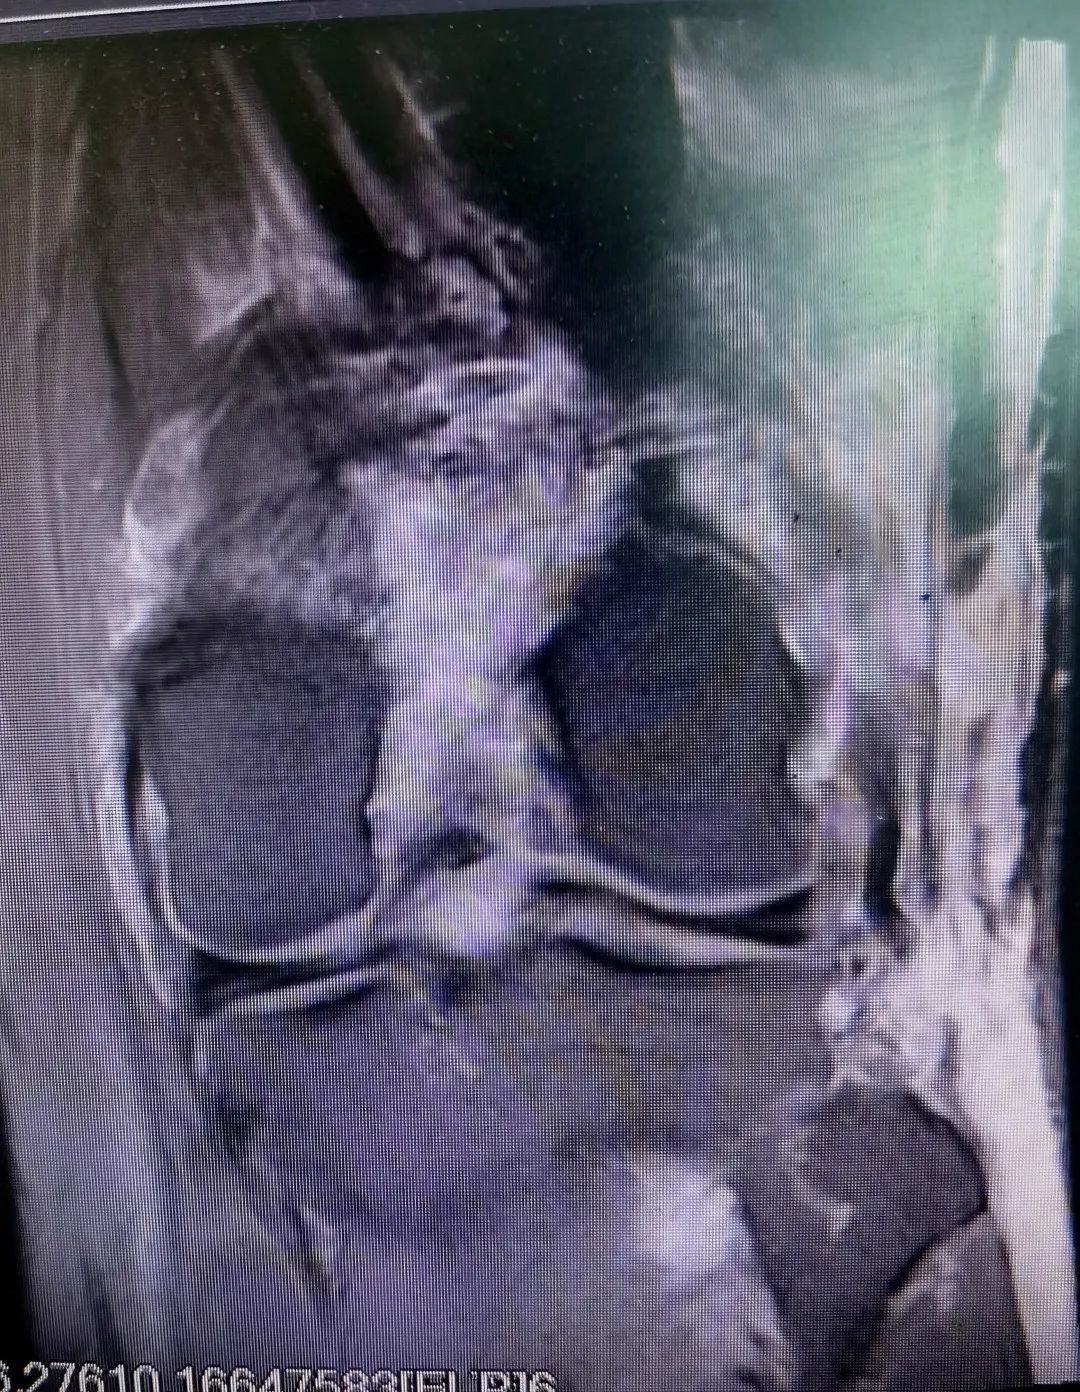

患者受伤部位肿胀畸形,已经严重到无法行走的程度,骨科医师经过仔细体查并结合辅助检查结果,诊断陈先生为 “1、左膝关节多发韧带损伤:前交叉韧带断裂,后交叉韧带断裂;2.后外侧复合体损伤:外侧副韧带损伤,腓肠肌外侧头止点损伤,股二头肌止点损伤,关节囊撕裂;3、腓总神经损伤”,建议行手术治疗,陈先生及家属表示理解并同意手术。

手术当天,麻醉医师给患者进行“腰硬联合麻醉”后,医院骨伤关节科团队邹晖主任带领袁雄、杨奇、罗毅医师一起在陈先生的左膝关节前内侧和前外侧入路各开一0.8厘米入口直达关节腔,在关节镜下一期重建了前交叉韧带、后交叉韧带,修复了外侧副韧带、腓肠肌外侧头止点、股二头肌止点,修复了关节囊,同时探查了腓总神经,整个复杂的手术过程一气呵成。目前,患者病情正在恢复中,患者主管医师预计手术6周后,陈先生可以进行日常活动。